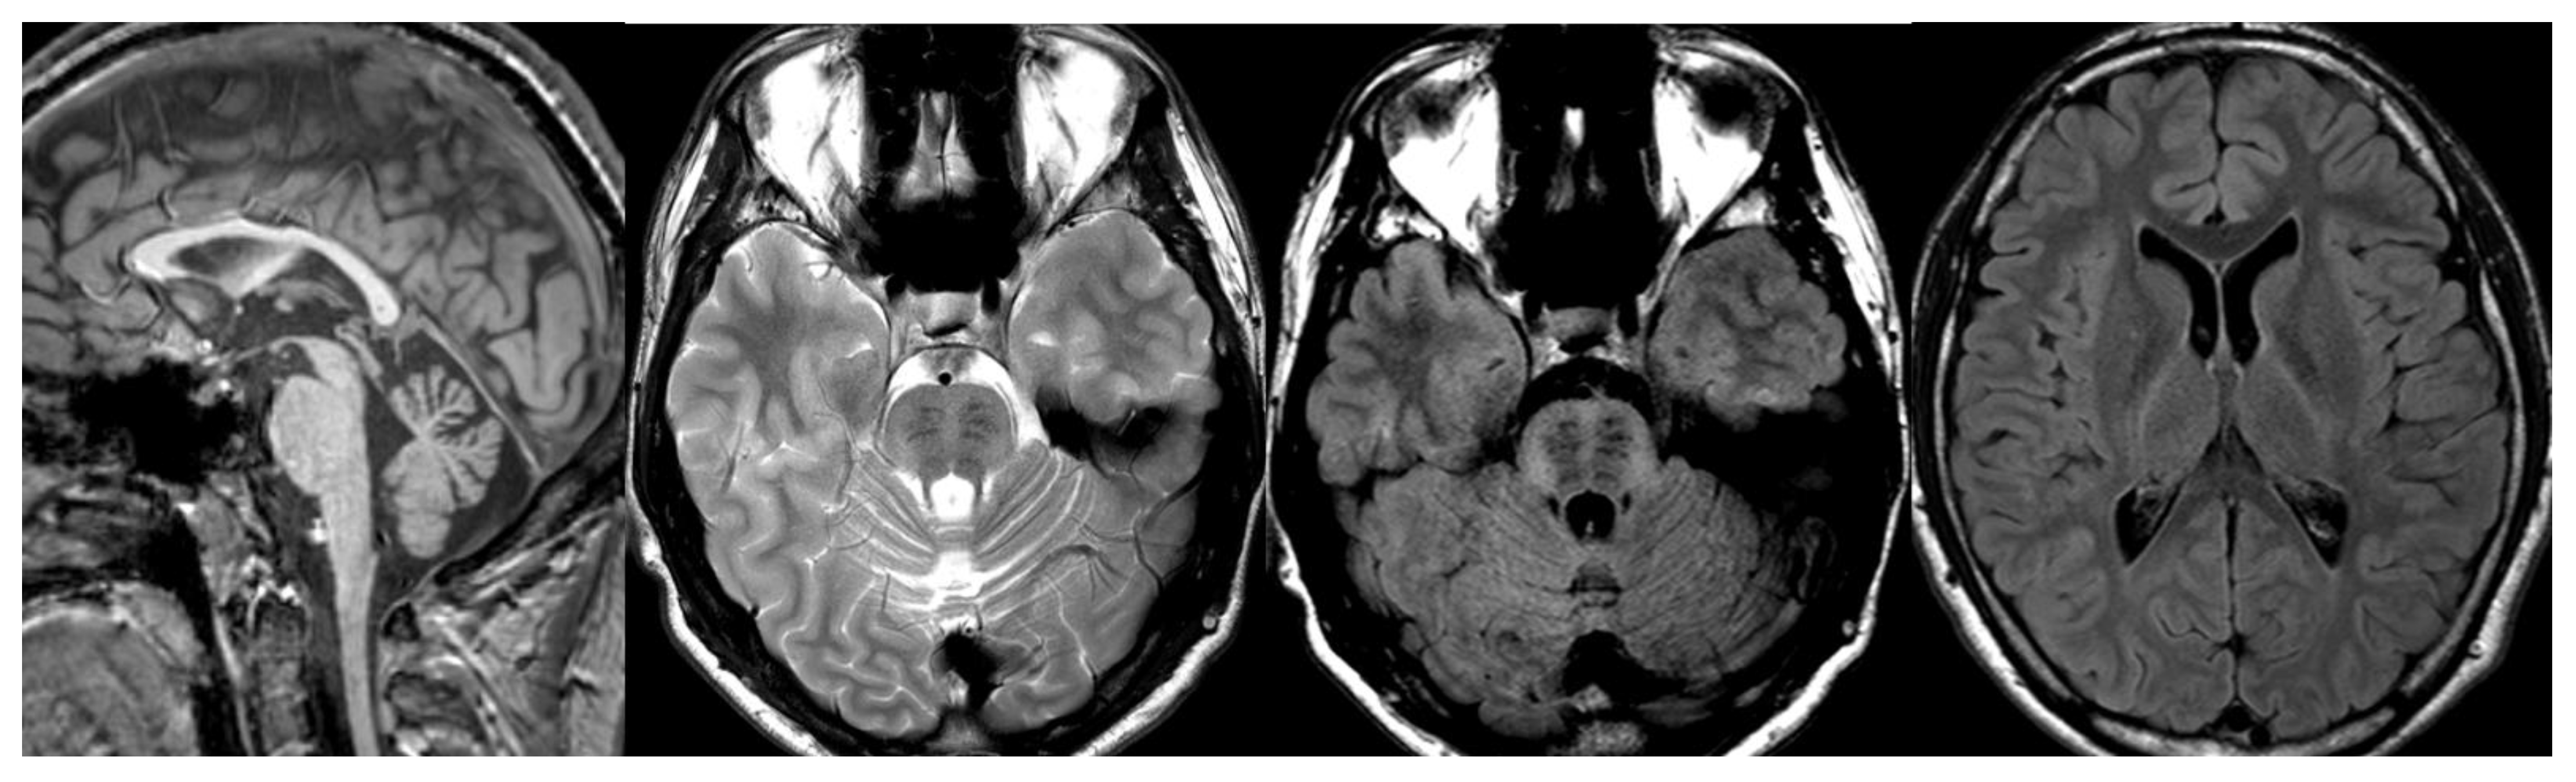

Isolated or predominant cerebellar volume loss due to cerebellar hypoplasia or, more frequently, progressive cerebellar atrophy are common neuroradiological features in children with various mitochondrial disorders: complex I, complex II, complex III and complex IV deficiency, isolated or combined, multiple respiratory chain defects (RCDs) and partial coenzyme Q10 deficiency [44] (Figure 8).

Figure 8.

Coenzyme Q10 deficiency. Brain MRI scan of a 15-year-old girl. MR images demonstrate not specific diffuse cerebellar atrophy and a normal volume of the brainstem.

Coenzyme Q10 transfers electrons along the respiratory chain; among other clinical manifestations, Coenzyme Q10 deficiency has been associated with cerebellar ataxia [45]; 13 genes encode proteins involved in its biosynthesis, but only mutations in 10 genes have been associated with diseases. One of the most well-documented is mutations in the COQ8A gene (formerly ADCK3). In these patients, cerebellar atrophy is an almost universal finding [46].

CACNA1G calcium channel is known to cause adult-onset spinocerebellar ataxia [42]; recent works report cerebellar ataxia associate with mutations in this gene [48,49]. MRI shows cerebellar atrophy [49] (Figure 9).

Figure 9.

CACNA1G mutation. Brain MRI scan of an 11-year-old girl. MR images demonstrate not specific diffuse cerebellar atrophy.

2.2. H-ABC (Hypomyelination with Atrophy of Basal Ganglia and Cerebellum)

H-ABC is an autosomal dominant hypomyelination leukodystrophy due to TUBB4A mutations [52]. The characteristic clinical features are progressive dystonia with early onset associated with cerebellar and pyramidal signs and cognitive deficiency. Neuroradiological findings combine diffuse cerebellar atrophy, hypomyelination, and typical basal ganglia abnormalities characterized by progressive neostriatal atrophy, with a normal size of the pallidum and thalamus, until almost complete disappearance of the putamina and caudate [53] (Figure 10).

Figure 10.

HABC. Brain MRI scan of a 6-year-old girl. MR images show an almost complete lack of myelin, characterized by a strikingly hyperintense signal on a T2-weighted image. At this age, the putamen and caudate nucleus are normal-sized. Note the global cerebellar atrophy.

Neuroimaging demonstrates cerebello-vermian atrophy with normal basal ganglia and T2 hyperintensity of middle cerebellar peduncles. Cases with POLR3A demonstrate less cerebellar atrophy, while cases with POLR3B show subtler degrees of hypomyelination 27 (Figure 11).

Figure 11.

POLR3B mutation. Brain MRI scan of a 10-year-old girl. MR images show marked global cerebellar atrophy with a thin corpus callosum and hypomyelination throughout the white matter, both cerebral and cerebellar.